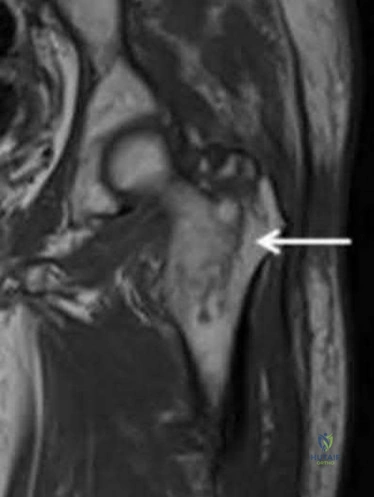

Question 14:

A 22-year-old football player sustains a recurrent anterior shoulder dislocation. An MRI arthrogram reveals a Bankart tear and a large Hill-Sachs lesion that engages the anterior glenoid rim. What is the best surgical option to address the engaging Hill-Sachs lesion?

Correct Answer: Remplissage procedure with Bankart repair

Explanation:

An engaging Hill-Sachs lesion is a defect on the posterolateral humeral head that engages the anterior glenoid during abduction and external rotation, predisposing to recurrent dislocation. The Remplissage procedure (infilling the defect with the infraspinatus tendon and capsule) combined with a Bankart repair is an effective treatment.